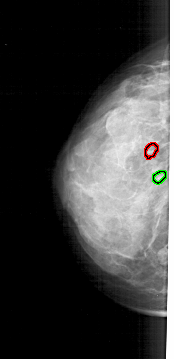

A_1721_1.LEFT_MLO

LEFT_MLO LINES 5386 PIXELS_PER_LINE 2281 BITS_PER_PIXEL 12 RESOLUTION 43.5 OVERLAY

FILE: A_1721_1.LEFT_MLO.OVERLAY

TOTAL_ABNORMALITIES 2

ABNORMALITY 1

LESION_TYPE CALCIFICATION TYPE PLEOMORPHIC DISTRIBUTION CLUSTERED

ASSESSMENT 4

SUBTLETY 3

PATHOLOGY MALIGNANT

TOTAL_OUTLINES 1

BOUNDARY

ABNORMALITY 2